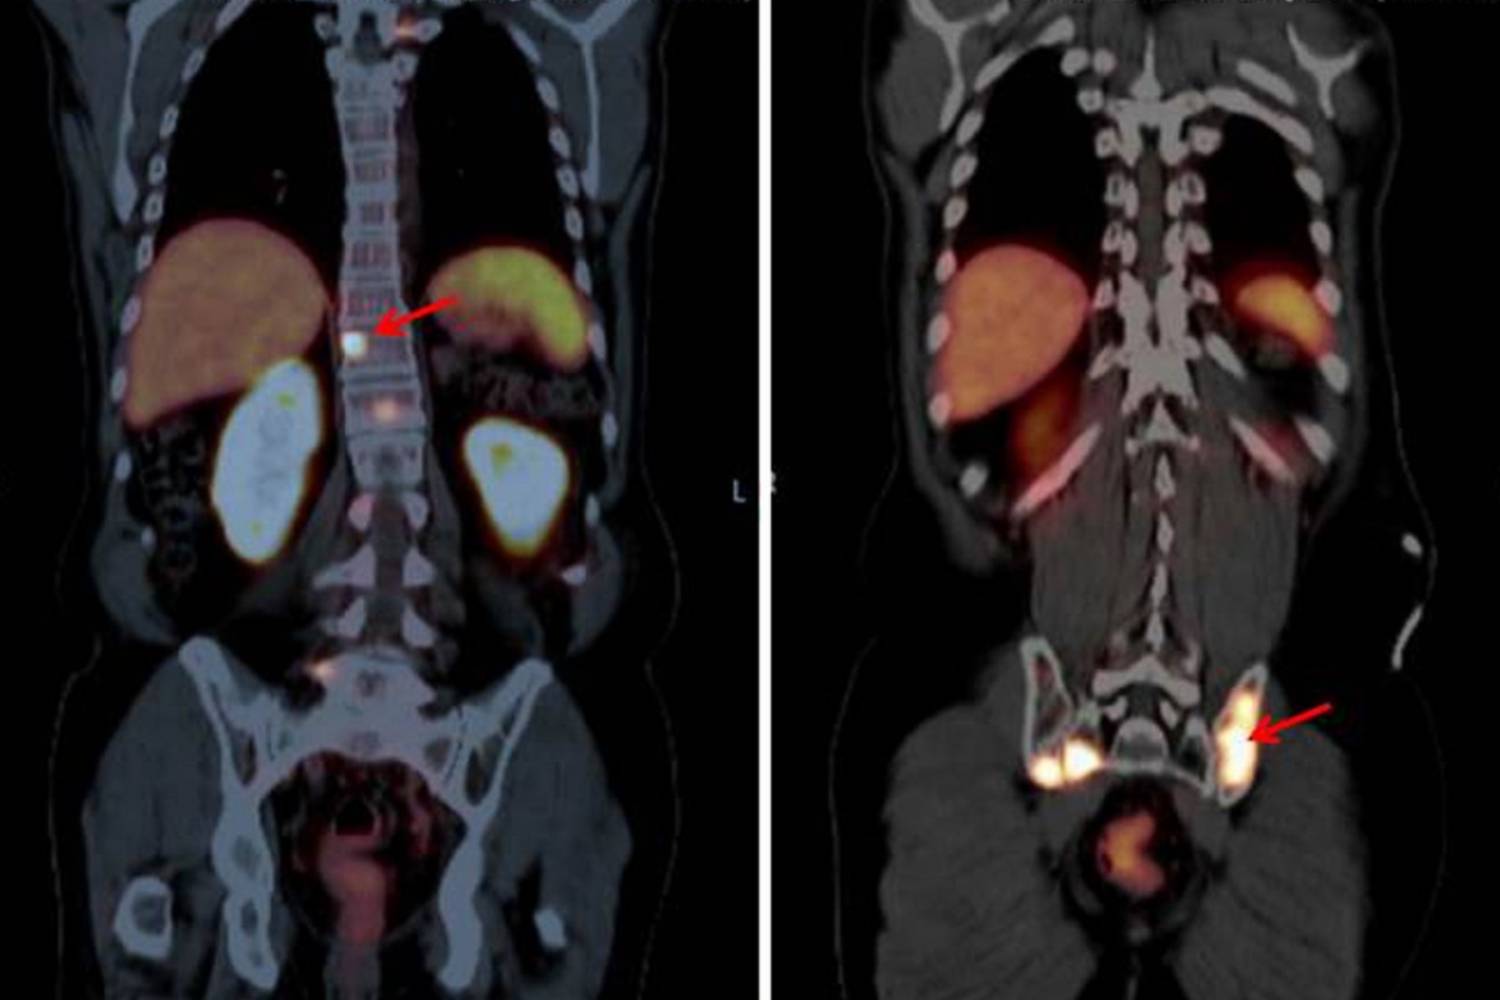

Investigaciones previas han demostrado que la terapia dirigida con PSMA (Antígeno de Membrana Específico de la Próstata) para el cáncer de próstata puede prolongar la vida de pacientes que han agotado todas las demás opciones de tratamiento. Esta estrategia dirigida de vanguardia con radioligandos se considera en cáncer de próstata avanzado, metastásico y resistente a la castración. Sin embargo, un nuevo estudio demuestra ahora que también es eficaz en una etapa más temprana de la enfermedad prostática.

Como resultado, la terapia hormonal, más compleja, puede posponerse hasta veinte meses adicionales, según los datos de una investigación multicéntrica dirigida desde el Hospital Radboudumc, de la Universidad de Radboud, en Países Bajos y publicado en The Lancet Oncology.